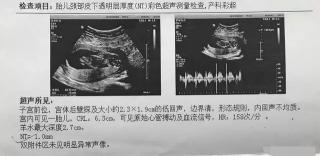

怀孕3个月,这时候就该去建档了,此前没有做过产检的,这个月也必须做第一次产检。我在3个月是做了第二次产检的,当时的B超主要是做NT,当然,基本的指标也都是全的。可以参考一下我的B超单,主要有以下内容。

宫体后壁探及2.3*1.9厘米的低回声,这说明胎盘是位于子宫后壁的。相对于51天的数据来说,这个尺寸变化不大,51天是1.5*1.9厘米。

宫内可见一个胎儿,有几个胎儿就写几个胎儿。这个马虎不得,这时候B超已经能非常明确胎儿的个数了,不会有错。

可以根据CRL的尺寸计算孕周,公式是:6.5+CRL。我这个的尺寸是6.3厘米,计算孕周是12.8周,按末次月经计算的孕周是13周+天,是有一定差距的。

这时已经能测到胎儿的胎心率了,B超单上写着“可见原始心管搏动及血流信号,HR158次/分,也就是胎心率多少。胎心率在120-160次/分都是正常的。

羊水最大深度,表示羊水最深量,有的报告单也叫羊水暗区。正常范围是3-8厘米。我这个是2.7厘米,但是医生也没说不正常,而且后期也都是很正常的,所以这时不用担心。

胎儿颈部以下液体的厚度,小于3毫米,说明患有唐氏综合征的风险较低,95%的孕妈妈都是这个样的结果。如果大于3毫米,患有唐氏综合征的风险较高,后期需要做无创或羊水穿刺进一步判断。我的是1mm,我是高龄产妇,做了无创,一次性低风险通过。